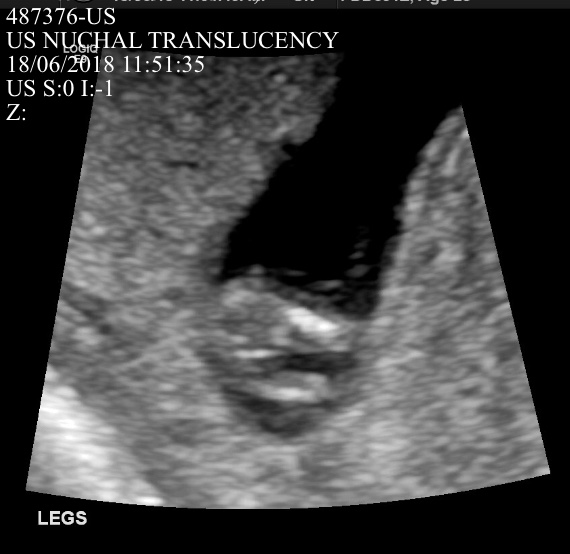

Hi guys. I’m posting 2 profile photos and 2 potty shots from my 12 week scan (measure 12w1d). I am not sure if either of the profile photos show a nub - if so, what are your guesses based on either of the profile photos or the potty shot?

I see 3 lines in the potty shot but the middle line is much longer pointing out. I will update on Friday when I find out but would love some guesses until then. TIA. Attachment 39791Attachment 39792Attachment 39793Attachment 39794